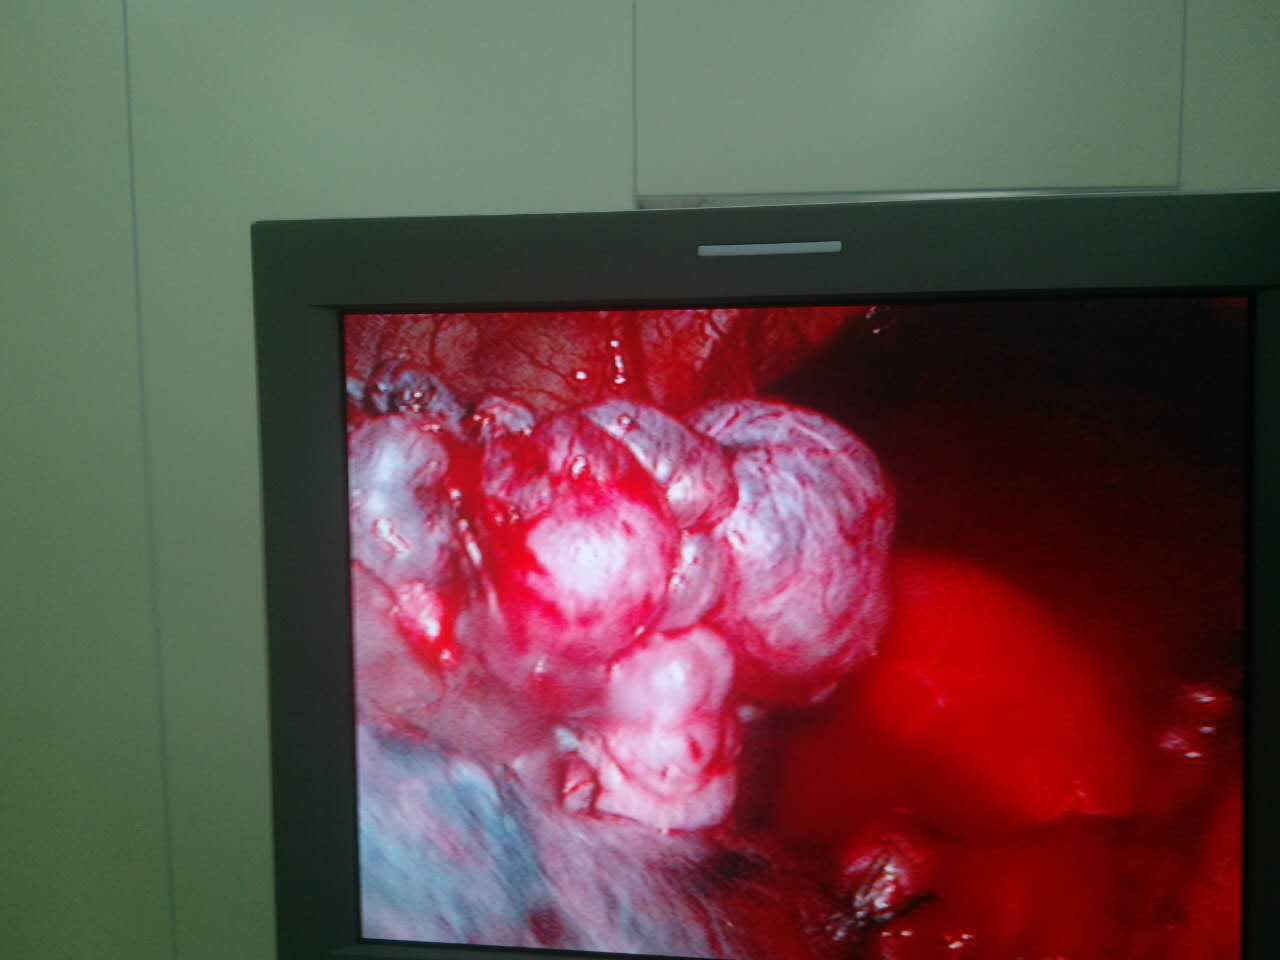

肺大疱的胸腔镜下观

胸腔镜下肺大泡切除术

胸腔镜下肺大泡切除术:图片展示_积气